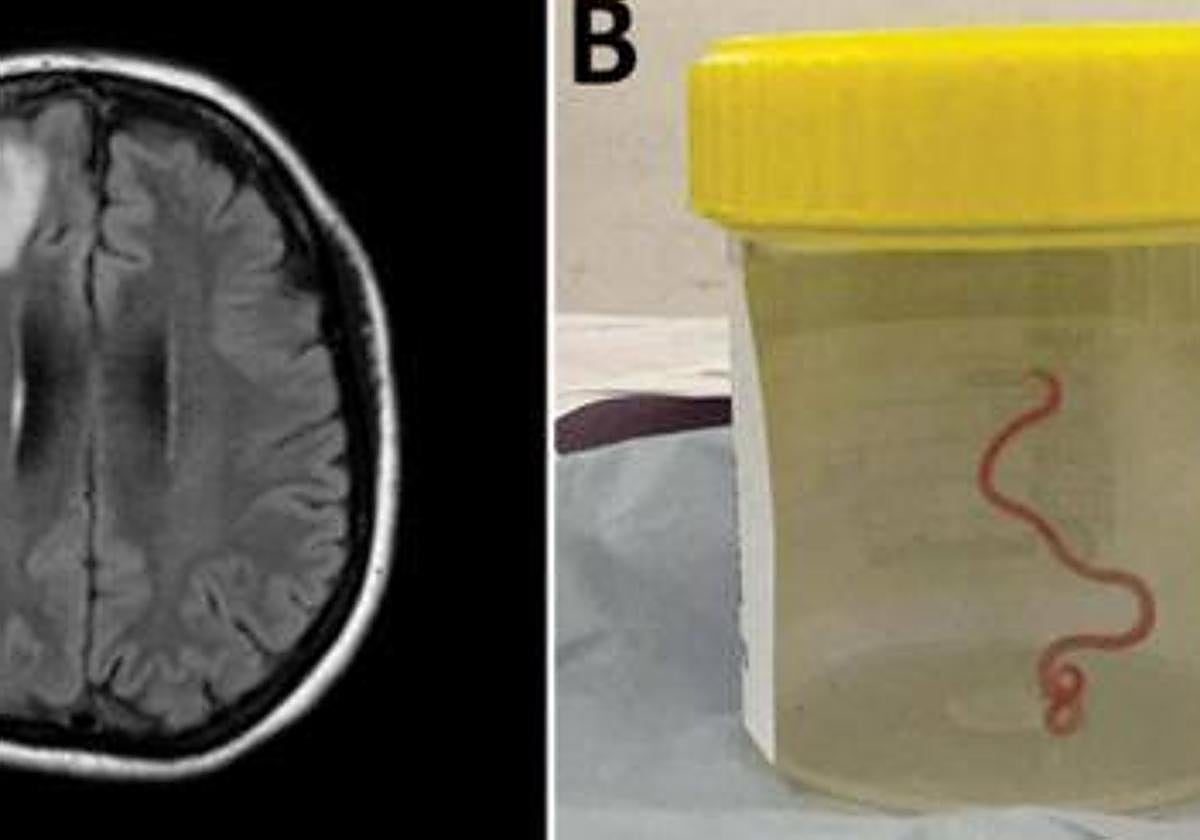

Iniciar sesiónViva y retorciéndose. Así extrajeron una lombriz del cerebro de una mujer australiana en el Hospital de Canberra, donde acudió aquejada de dolor abdominal, diarrea, tos y sudores nocturnos. El parásito medía ocho centímetros y procedía de una pitón de alfombra y los médicos sospechan ... que también había larvas o ejemplares jóvenes en otros órganos del cuerpo de la paciente, como los pulmones y el hígado.

En 2022, empezó a experimentar cambios sutiles en la memoria y el procesamiento del pensamiento, así como depresión, y se sometió a una resonancia magnética cerebral que demostró una lesión atípica en el lóbulo frontal derecho del cerebro.

Un neurocirujano del Hospital de Canberra exploró la anomalía y fue entonces cuando encontró la inesperada lombriz, de ocho centímetros. Su identidad fue confirmada posteriormente por expertos en parasitología, inicialmente por su aspecto y luego mediante estudios moleculares.